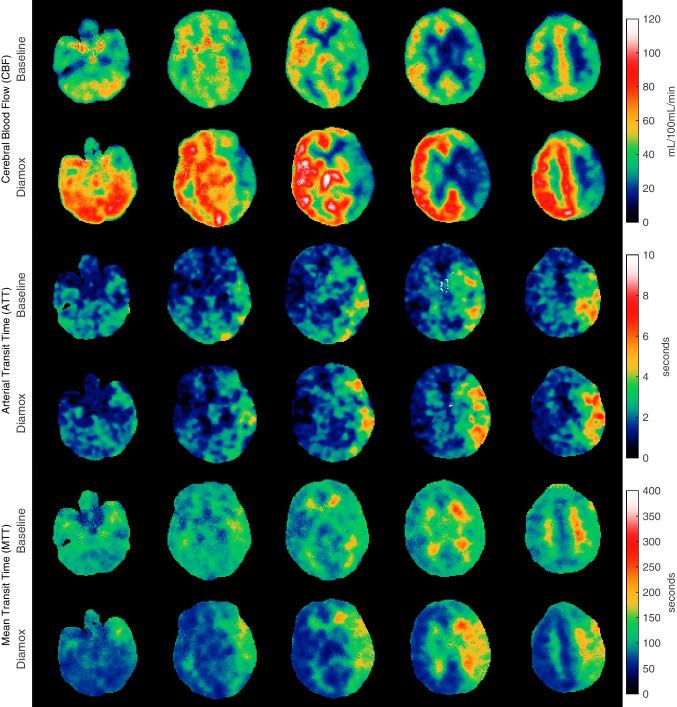

New total-body PET scanners with a long axial field of view (LAFOV) allow for higher temporal resolution due to higher sensitivity, which facilitates perfusion estimation by model-free deconvolution. Fundamental tracer kinetic theory predicts that perfusion can be estimated for all tracers despite their different fates given sufficiently high temporal resolution of 1 s or better, bypassing the need for compartment modelling. The aim of this study was to investigate whether brain perfusion could be estimated using model-free Tikhonov generalized deconvolution for five different PET tracers, [O]HO, [C]PIB, [F]FE-PE2I, [F]FDG and [F]FET. To our knowledge, this is the first example of a general model-free approach to estimate cerebral blood flow (CBF) from PET data.

Twenty-five patients underwent dynamic LAFOV PET scanning (Siemens, Quadra). PET images were reconstructed with an isotropic voxel resolution of 1.65 mm. Time framing was 40 × 1 s during bolus passage followed by increasing framing up to 60 min. AIF was obtained from the descending aorta. Both voxel- and region-based calculations of perfusion in the thalamus were performed using the Tikhonov method. The residue impulse response function was used to estimate the extraction fraction of tracer leakage across the blood-brain barrier.

CBF ranged from 37 to 69 mL blood min 100 mL of tissue in the thalamus. Voxelwise calculation of CBF resulted in CBF maps in the physiologically normal range. The extraction fractions of [O]HO, [F]FE-PE2I, [C]PIB, [F]FDG and [F]FET in the thalamus were 0.95, 0.78, 0.62, 0.19 and 0.03, respectively.

The high temporal resolution and sensitivity associated with LAFOV PET scanners allow for noninvasive perfusion estimation of multiple tracers. The method provides an estimation of the residue impulse response function, from which the fate of the tracer can be studied, including the extraction fraction, influx constant, volume of distribution and transit time distribution, providing detailed physiological insight into normal and pathologic tissue.